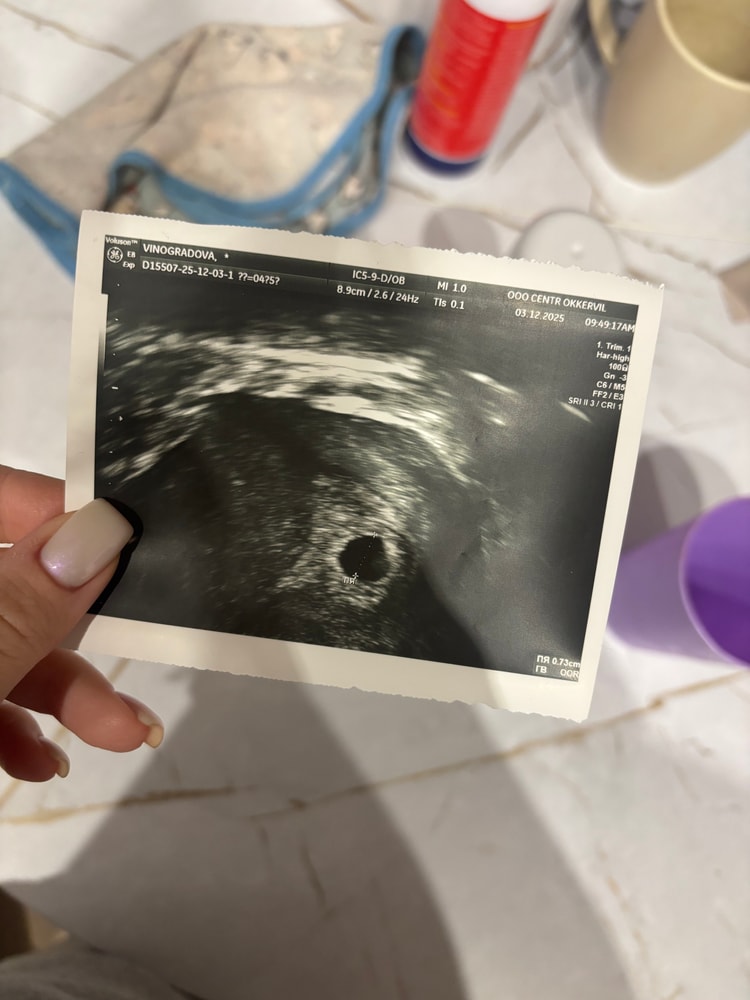

Вчера была на узи , 15 дпп. Хгч 10700. Плодное яйцо 7,3. ЖМ если и видно , то супер микроскопическим , и это был экспертный аппарат. Через неделю пойду пересматривать. Особой паники нет, понимаю , что далеко не всегда на таких маленьких пя есть жм . При 10 мм с дочкой уже был жм 2,7 . Но у меня есть проблема , что прогестерон 18 , и беременность эко на згт , когда нет своего желтого тела , и держится малыш на честном слове , естественно периодически подкравливает. Сейчас понимаю , что еще рано) думаю и у вас еще рано) Изображение

Дарья , у меня пя уже 17 мм. Жм нет. Регресс желтого тела и начало отслойки. Так что все тут понятно. Но виднла много случаев с положительным исходом. Искренне желаю Вам такой!